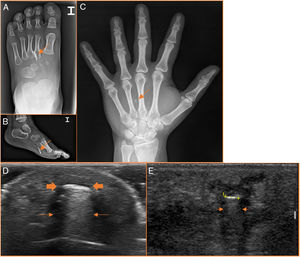

Plant-basedDetection with X-rayWooden splinters and thorns from different plants are not visible on X-rays (Fig. 4).16–19 They can only be suspected due to the increase of associated soft tissue.

Plant-based foreign bodies are radiolucent. (A and B) The palm tree thorn is not visible on X-ray, but there is an increase of soft tissue (arrows) in the proximal phalanx of the third finger. (D–F) On ultrasound, they are slightly hyperechogenic (thick arrows in D and E) and their echogenicity reduces over time (cursors in F). The surrounding hypoechoic rim is very pronounced in plant-based foreign bodies (thin arrows).

Splinters and thorns are generally hyperechogenic, although less so than the other foreign bodies already discussed. They present deep posterior acoustic shadowing and of variable density (Fig. 4).17,20,21 Wood and other organic foreign bodies lose echogenicity over time.3,16,19 The secondary inflammatory process, reflected in the surrounding hypoechoic rim and the increase of the Doppler signal, is more evident and develops more quickly with organic materials (plants, wood) and with contaminated inorganic materials (metal, glass).3,16,20